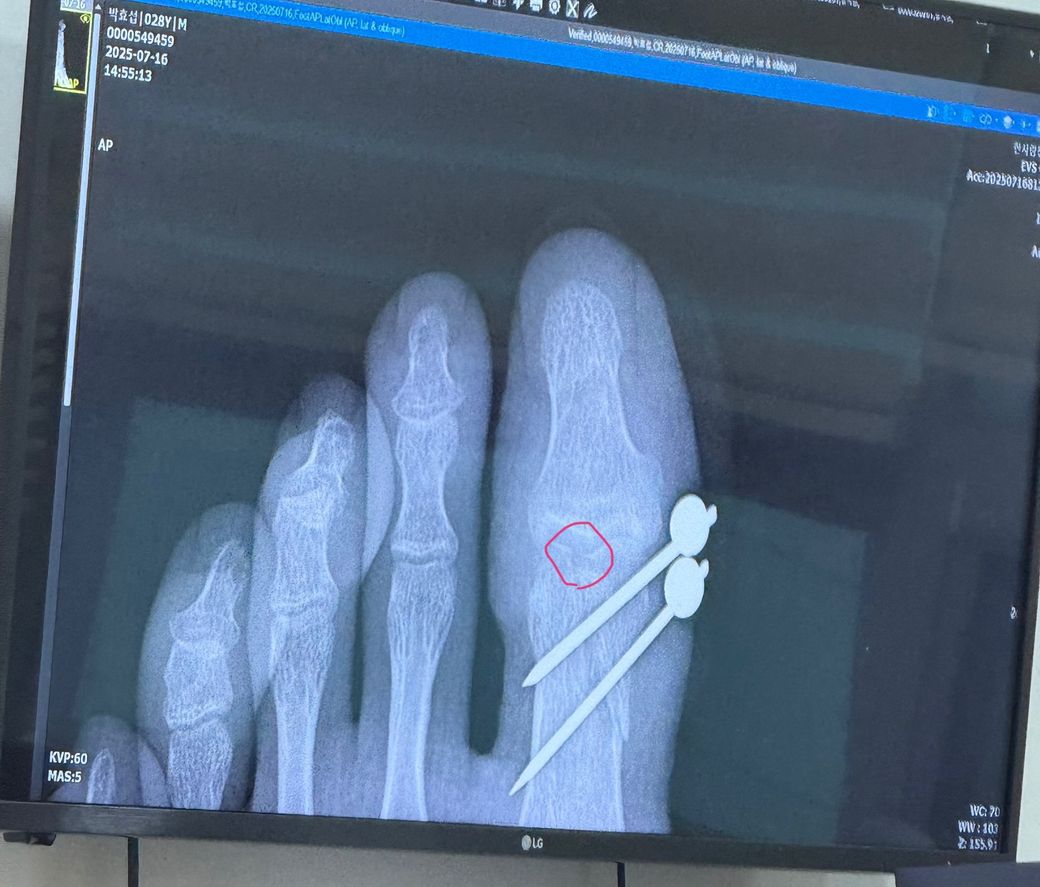

왼쪽엄지발가락 골절수술 5주차 핀제거

핀수술 5주차인 현재 핀제거를 했습니다.

근데 엑스레이를 보니 골절된 윗쪽 관절면이 매끄럽지 못하고 단차가 된상태로 붙은거같습니다..

재수술이나, 합병증이 올까봐 무섭습니다.

대학병원을 내방해야하나요?

골절자체가 관절면을 침범하였기 때문에

관절염은 피할수가 없습니다.

사진상으로 보이는 간격은 문제가 될만한 간격으로 보이진 않는것 같습니다.